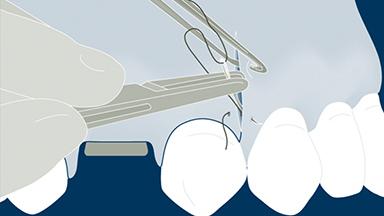

Suturing Materials and Techniques

Each procedure creates a wound. For optimal healing, surgical flaps - and often other surgical wounds - must be properly closed with sutures.

Satisfactory closure of surgical wounds and flaps promotes healing and reduces complications such as wound breakdown, dehiscence, and infection.

This module will present the appropriate materials and proper techniques for suturing that contribute to a successful outcome, as well as the improper techniques that can lead to potential complications.